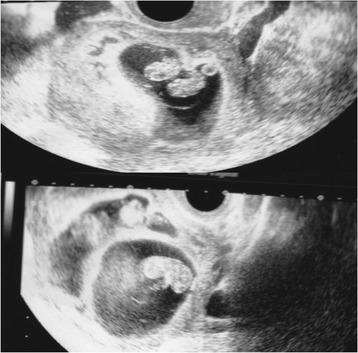

We describe two cases of dichorionic triplet pregnancy after a frozen-thawed poor-stage embryo transfer. A 39-year-old and a 41-year-old woman underwent ART treatment. The first patient underwent intracytoplasmic sperm injection (ICSI) at 34 years of age, and two frozen-thawed poor-stage embryos were transferred at 39 years of age with assisted hatching, resulting in a trichorionic triamniotic triplet pregnancy. The second patient underwent ICSI, and two poor-grade blastocysts were transferred followed by assisted hatching, resulting in a dichorionic triamniotic triplet pregnancy. In the first case, the heartbeat of one monozygotic twin fetus had stopped on day 48 post-transfer (9 weeks 2 days), resulting in a dichorionic diamniotic twin pregnancy. A healthy boy and girl were delivered by elective caesarean section at 36 weeks, 5-days gestation. In the second case, the patient underwent selective reduction of the monochorionic twins, resulting in a single pregnancy that was vaginally delivered without any problems at 38 weeks 0-days gestation.

我们描述了两例冻融低质量胚胎移植后双绒毛膜三胎妊娠的病例。一名39岁和一名41岁的女性接受了辅助生殖技术治疗。第一名患者34岁时接受了卵胞浆内单精子注射(ICSI),39岁时移植了两枚冻融低质量胚胎并进行了辅助孵化,结果是三绒毛膜三羊膜囊三胎妊娠。第二名患者接受了ICSI,随后移植了两枚低质量囊胚并进行了辅助孵化,结果是双绒毛膜三羊膜囊三胎妊娠。在第一例中,一个单卵双胎胎儿的心跳在移植后第48天(9周2天)停止,导致双绒毛膜双羊膜囊双胎妊娠。在妊娠36周5天时通过择期剖宫产分娩了一名健康男婴和一名健康女婴。在第二例中,患者对单绒毛膜双胎进行了选择性减胎,结果是单胎妊娠,并在妊娠38周0天时顺利阴道分娩。